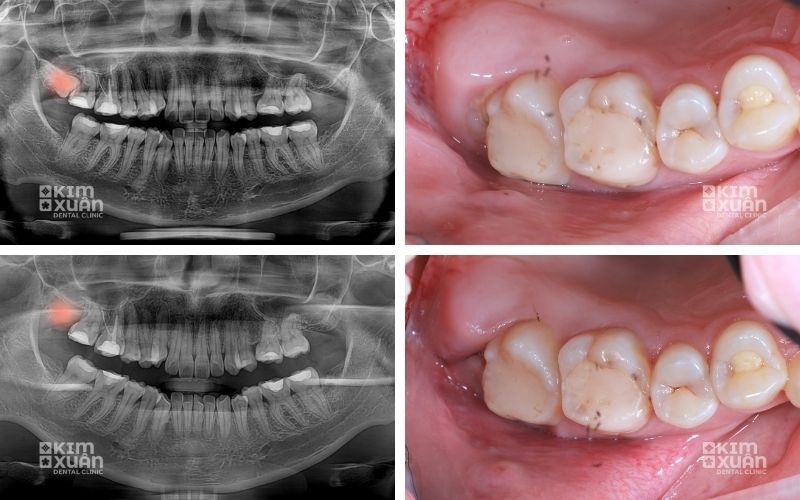

6. Cách Nhận Biết Răng Khôn Mọc Ngầm Chính Xác

Để xác định răng khôn mọc ngầm, cần thực hiện các bước sau:

Thăm khám nha khoa định kỳ nhằm kiểm tra tình trạng nướu, vị trí răng khôn và phát hiện sớm các dấu hiệu bất thường.

Chụp X-quang răng để xác định chính xác vị trí răng khôn trong xương hàm, hướng mọc, mức độ mọc ngầm và mức độ ảnh hưởng đến răng kế cận.

Đánh giá tổng thể kết quả kiểm tra, từ đó bác sĩ sẽ tư vấn phương án theo dõi hoặc chỉ định điều trị phù hợp với từng trường hợp cụ thể.

Trong nhiều trường hợp, răng khôn mọc ngầm không gây đau nhức rõ ràng nên rất khó nhận biết bằng mắt thường hoặc tự kiểm tra tại nhà. Vì vậy, thăm khám nha khoa kết hợp chụp X-quang vẫn là phương pháp chính xác và an toàn nhất để phát hiện sớm và phòng ngừa biến chứng.